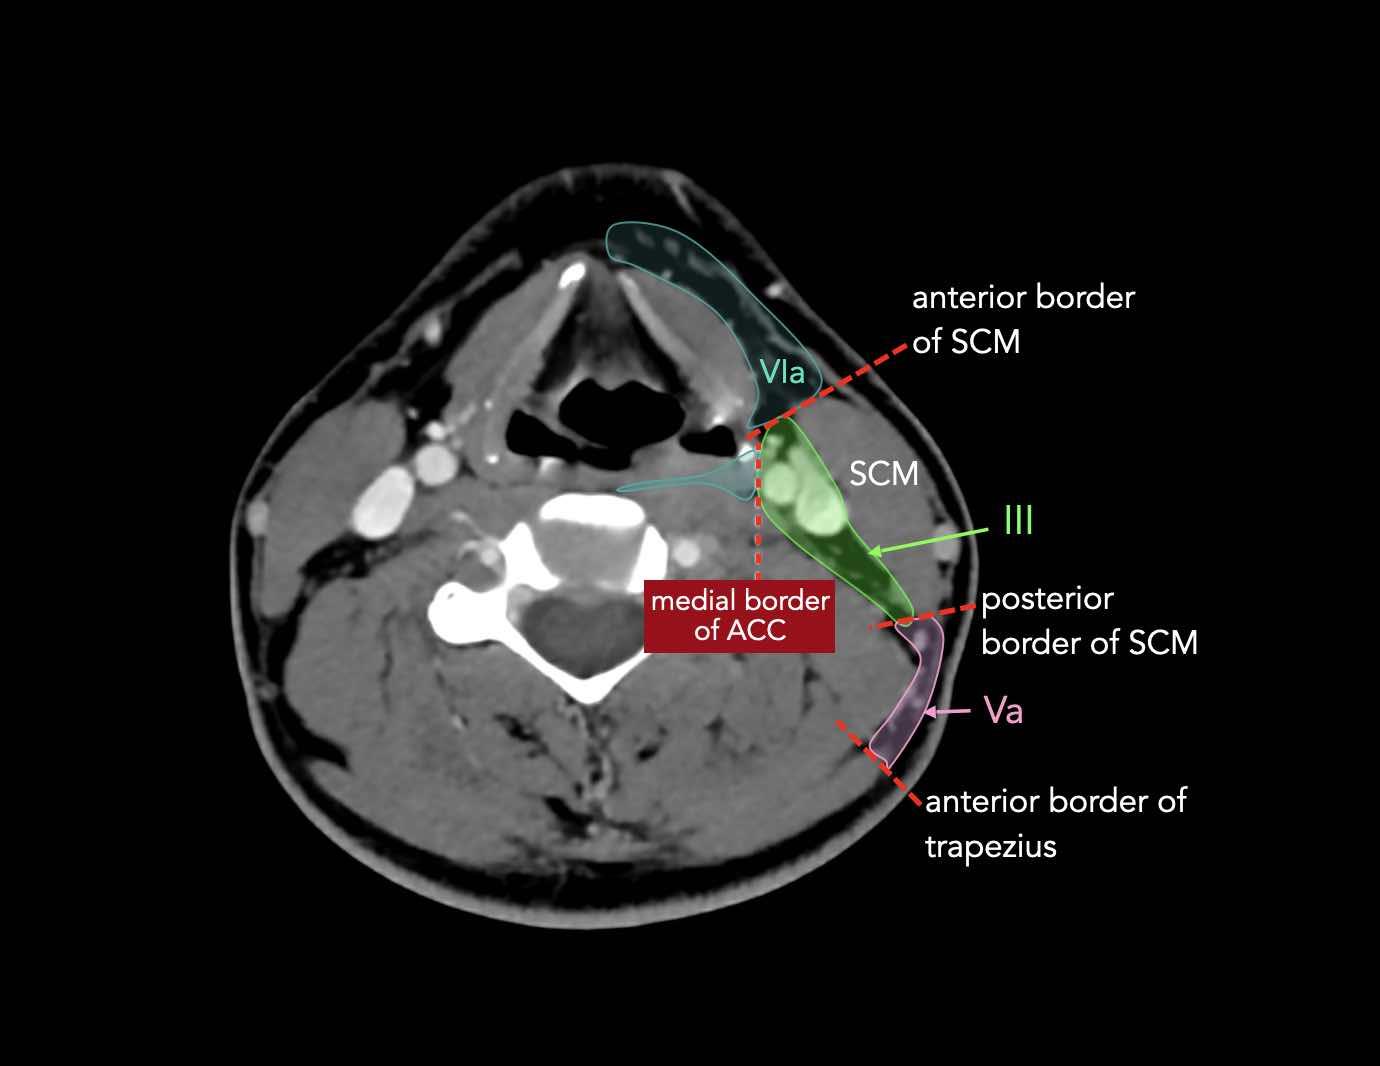

CT Scan Mặt Cắt Ngang (Axial CT)

Các lát cắt CT mặt phẳng ngang tương ứng với hình minh họa tổng quan.

Các lát cắt CT mặt phẳng ngang với hình ảnh chi tiết hơn.

Nhấp vào hình ảnh để phóng to.

III – Tĩnh mạch cảnh giữa

Các hạch bạch huyết ở tầng III có nguy cơ chứa di căn từ các ung thư khoang miệng, vòm hầu, hầu miệng, hạ hầu và thanh quản.

V – Tam giác cổ sau và hố thượng đòn

Tầng V chứa các hạch của nhóm tam giác cổ sau nằm ở phía sau cơ ức đòn chũm, xung quanh phần dưới của thần kinh phụ gai sống và các mạch máu cổ ngang.

VI – Cổ trước